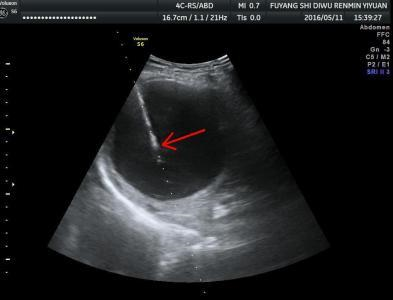

一、什么是肝、腎囊腫? 囊腫是一種較常見的良性病變,多數(shù)沒有癥狀,一般多在查體時發(fā)現(xiàn),可單發(fā)也可多發(fā),小的囊腫沒有任何癥狀,囊腫大時可出現(xiàn)壓迫癥狀。 二、肝腎囊腫的治療 原則上,囊腫5cm且有不適癥狀,那么可以考慮治療。 三、超聲介入治療肝腎囊腫的優(yōu)勢 超聲介入微創(chuàng)治療囊腫不用開刀,局部麻醉,穿刺針非常細,安全,痛苦小,療效好,并發(fā)癥非常少。